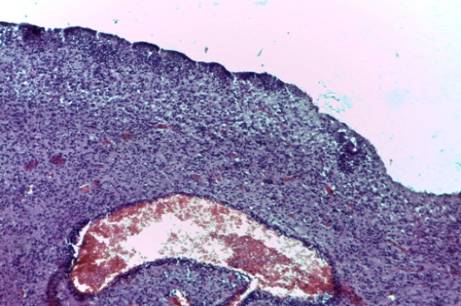

всех случаях имел место глиоз стволовой части мозга и субэпендимарной зоны,

причем глиоз в субэпендимарной зоне был

более выраженным (рис. №1). Во всех случаях имели место очаги

Рисунок

2- Глиоз в

субэпендимарной зоне

3. Маркерами тканевой

внутриутробной гипоксии явились глиоз

субэпендимарной и стволовой части мозга, очаги экстрамедуллярного кроветворения